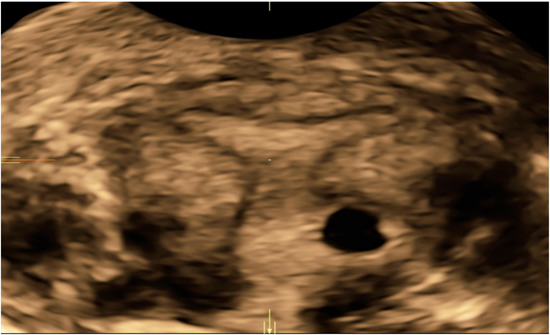

| Case 1 | Brownish vaginal discharge and mild pelvic pain | 7 | 18,048 | GS 15 × 14 mm right horn | MTX IM 50 mg/m2 of body surface | Complete resolution |

| Case 2 | Asymptomatic | 6 | 6579 | GS 6 × 8 mm; right horn | MTX IM 50 mg/m2 of body surface + Mifepristone 600 mcg | Complete resolution |

| Case 3 | Pinkish vaginal discharge | 5 + 3 | 2124 | GS right 12 × 12 horn; N/A | MTX IM 50 mg/m2 of body surface + Mifepristone 600 mg | Complete resolution |